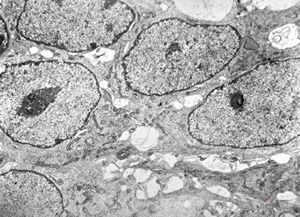

F,12y. | oligodendroglioma